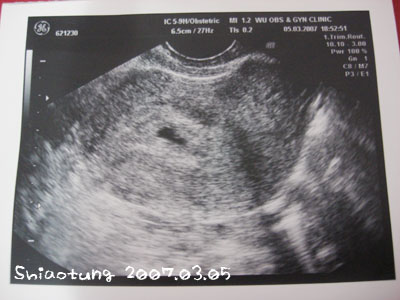

一進去醫生就要我內診,

果然就看到了那個可愛的小黑點。

真是很不起眼的小黑點...

我跟娘娘說:那黑點就是妳孫啦!

未滿四週

胖米:就是那一點黑黑的嗎?

阿爸:那個黑點喔?

娘娘:怎那麼大一點?

除了高興一直看著那張超音波照片上的黑點,